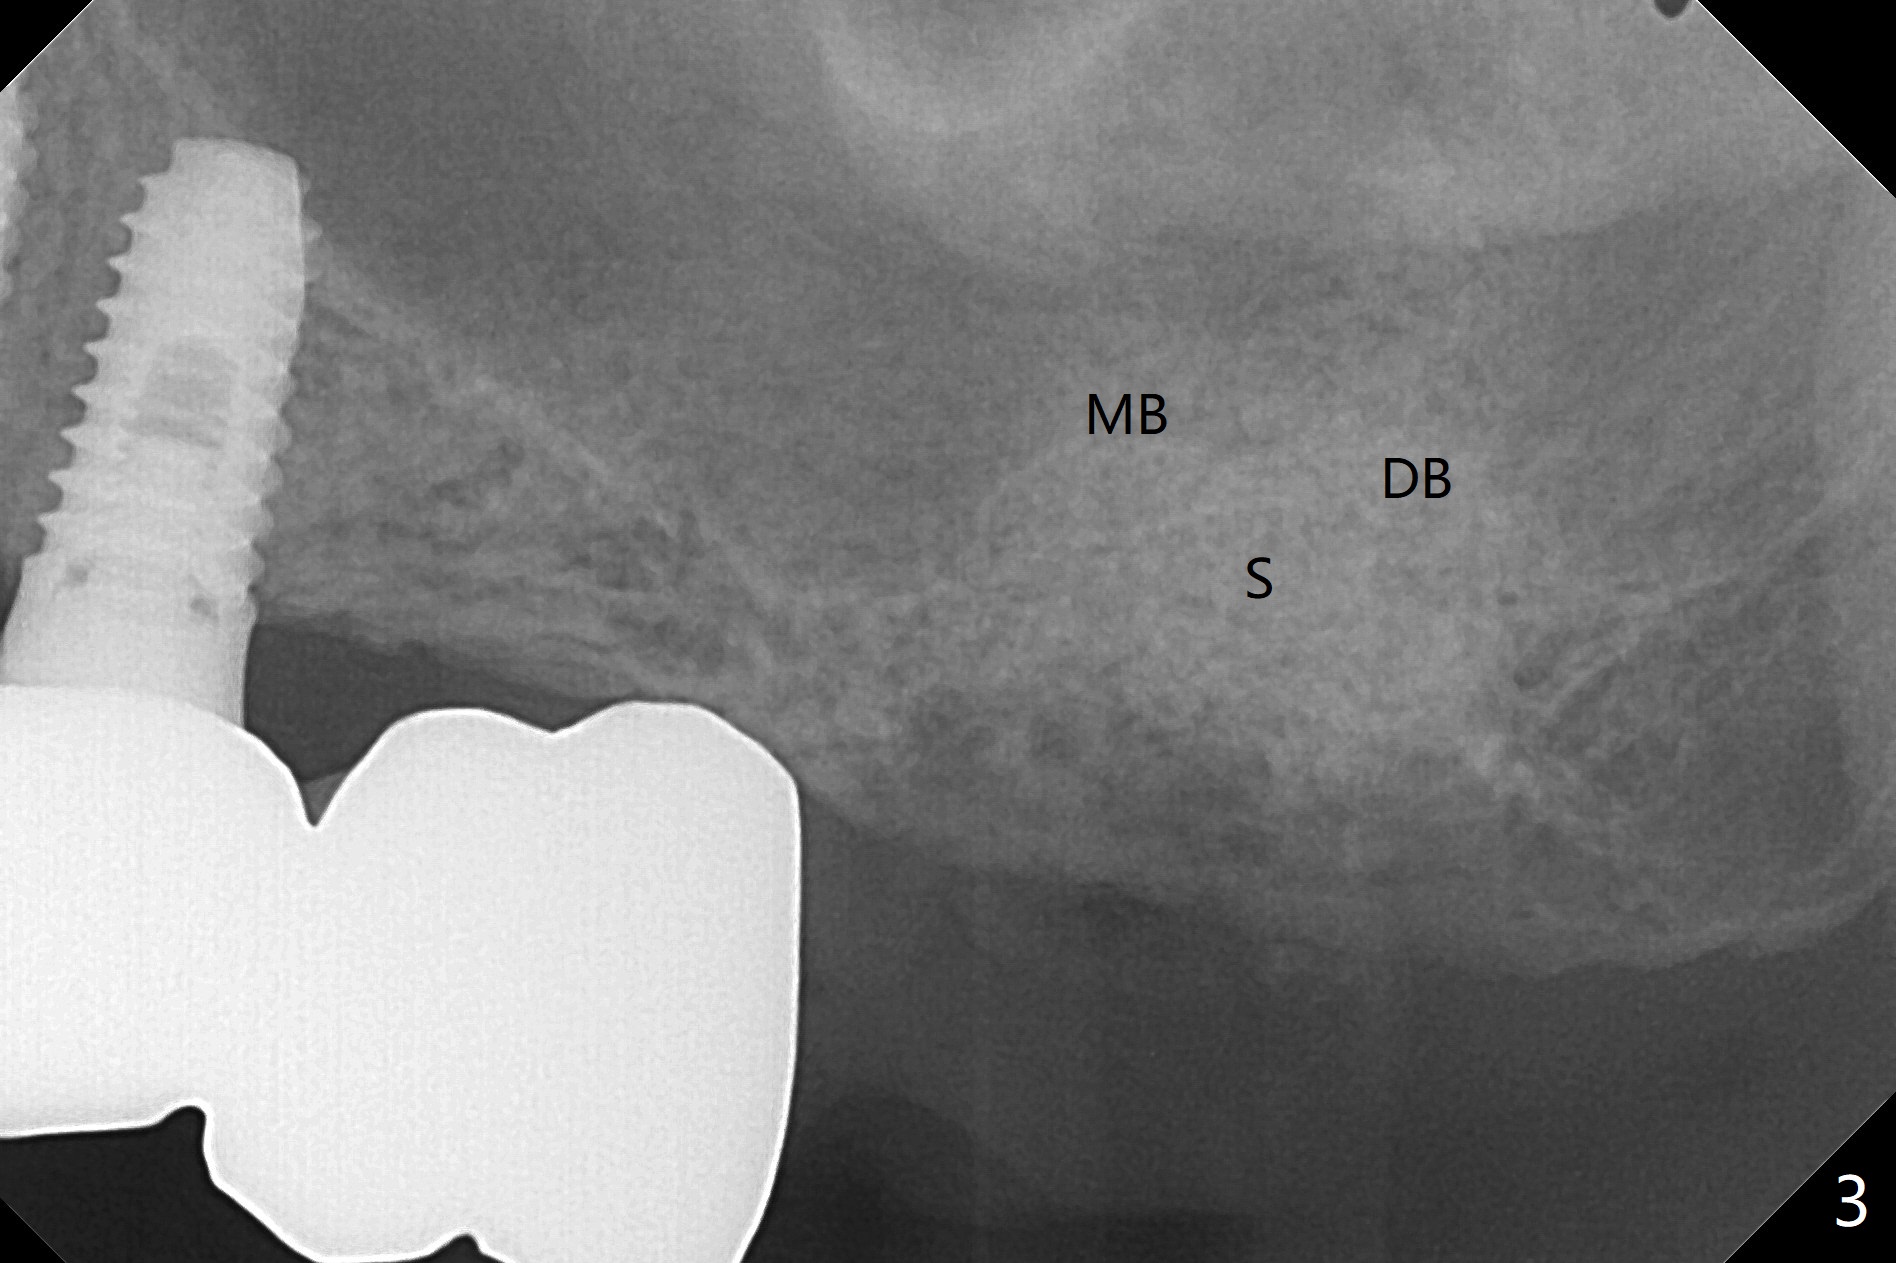

86岁男左上7折裂(图一),要求拔除,经过讨论(7拔除后,4-6悬臂桥可能断裂,对植体产生创伤,图二(左下7存在)),同意植骨。拔牙时发现中隔特别粗大(图三,五:S),三个牙槽窝根尖好像在中隔下面相互交通,擤鼻涕却没有气泡,仿佛与上颌窦没有相通。艰难清创后,放置Vanilla骨粉(图三),腭侧根特别容易填满,而颊侧根填入许多骨粉,术后CT远中颊侧骨粉尤其多(图四),上颌窦粘膜增厚(原来有季节性过敏)。术前根尖片显示远中颊侧根尖周围阴影很长(图五,六(虚线))。第二天早上鼻出血(仅有一次),今后牙槽窝明显比牙根长,清创控制深度,先放置胶原塞或PRF膜,后放骨粉。病人已经购买水牙线。术后7天树脂敷料稳定,局部卫生好(图七),骨粉好像进入上颌窦后部(图八)。术后1.5个月树脂敷料仍在原位,很容易撤除,牙槽窝愈合(图九),骨粉好像没有丢失(图十)。